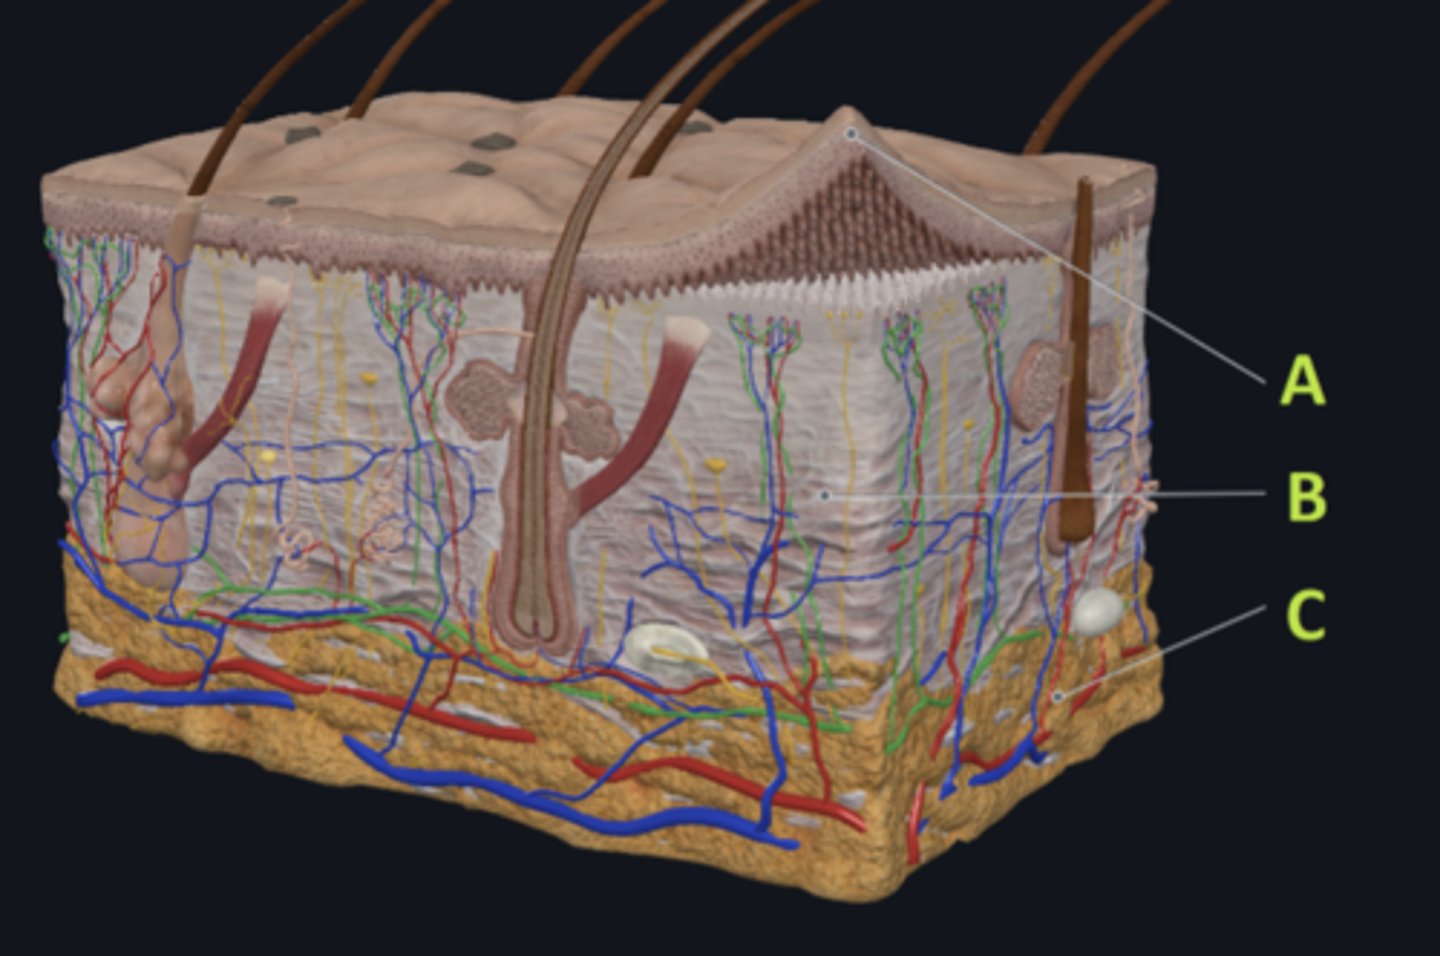

C - hypodermis

Answer the following questions based on the features indicated in the following image. Which letter indicates the administration site for subcutaneous injections?

A - epidermis

Answer the following questions based on the features indicated in the following image. Which letter indicates the administration site for topical creams and ointments?

B - Dermis

Answer the following questions based on the features indicated in the following image. Which letter indicates the administration site for the tuberculin skin test?

A - epidermis

Answer the following questions based on the features indicated in the following image. Which letter indicates a region of the skin with no nerves or blood vessels?

B - Dermis

Answer the following questions based on the features indicated in the following image. Which letter indicates the region where skin appendages (sweat glands, sebaceous glands, and hair follicles) have their roots?

Epithelial tissue

Answer the following questions based on the features indicated in the following image. Which of the four major tissue types is indicated by letter A?

Which letter indicates the administration site for insulin injections?

A

Which letter indicates the administration site for a lidocaine patch?

B

Which letter indicates the administration site for an allergy test?

B

Which letter indicates a region of the skin rich in dense, irregular connective tissue?

C

Which letter indicates the region most important for energy storage and thermal insulation?

Connective

Which of the four major tissue types is indicated by letter C?